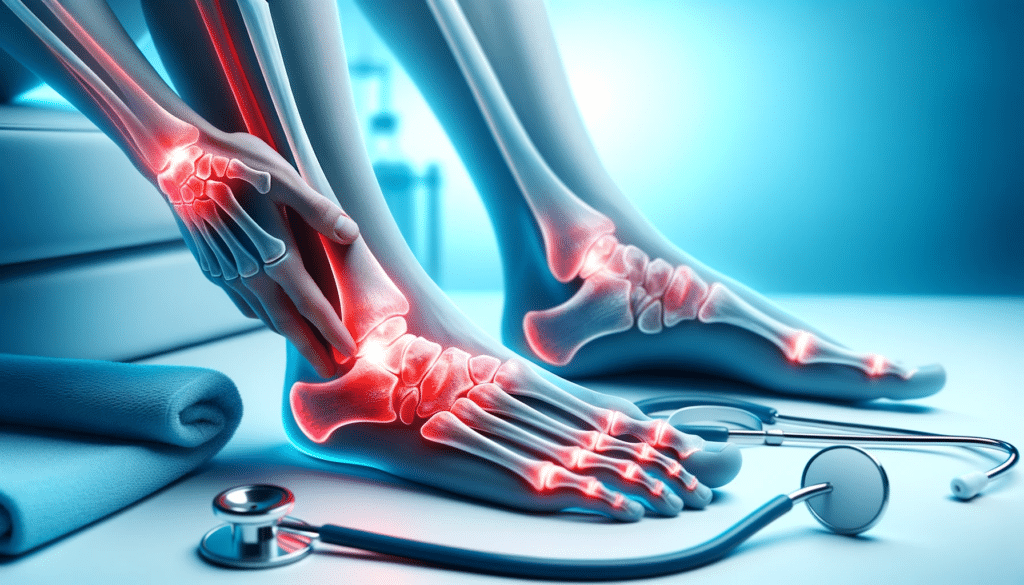

Se você já sentiu dor nos ossos dos pés, sabe o quão incômodo pode ser. A dor nos ossos do pé pode afetar a qualidade de vida, limitando a sua capacidade de caminhar ou realizar atividades físicas.

As causas da dor nos ossos dos pés podem variar desde o uso de sapatos inadequados até lesões por esforço repetitivo.

Algumas das principais causas incluem fraturas, metatarsalgia, fascite plantar e osteoporose. É indispensável procurar um ortopedista especialista em pé e tornozelo, como o Dr. Bruno Air, para avaliar a causa da sua dor e recomendar o tratamento adequado.

A dor nos ossos pode ser causada por lesões, inflamações, deformidades, sobrecarga, entre outras condições.

A dor nos ossos dos pés pode ser localizada em diferentes áreas, como no calcanhar, nas plantas dos pés, nos tornozelos e nas articulações.

A dor no pé pode ser leve ou intensa, e pode ser acompanhada de outros sintomas, como inchaço, vermelhidão, calor ou sensibilidade ao toque.